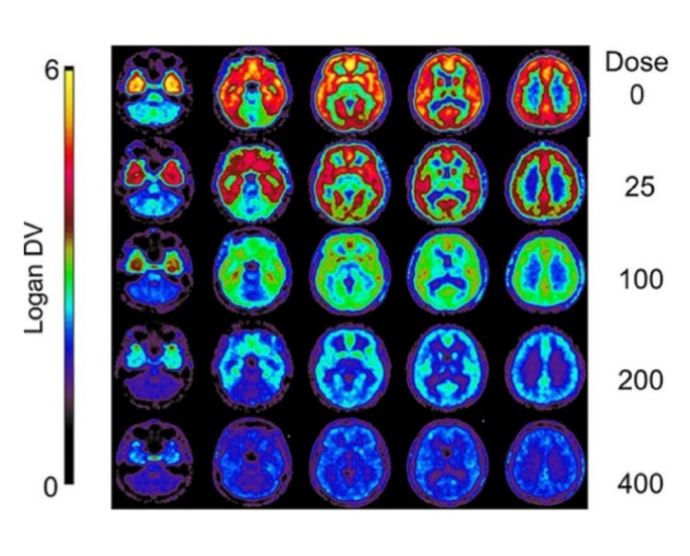

pmod’s tools provide comprehensive workflows for post-processing and quantification of imaging data for fundamental oncology research, development of radiotracers and theranostics, and in clinical research studies. Imaging scientists can trust pmod to reproducibly read their data, interpret the meta-data/units and help users calculate statistics such as SUV for their studies and publications.

Trusted quantification

For treatment evaluation and theranostic development

• Full access to metadata – ensure accurate calculation of Standard Uptake Value and other key statistics